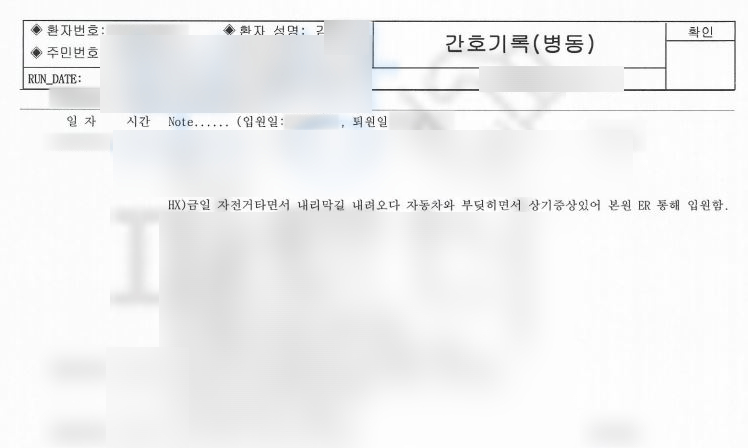

김@@님은 내리막길 자전거를 타고 내려가시다 마주 오는 차와 충돌하는 사고를 당하셨습니다.

심각한 허리 통증에 응급실로 내원하셨고 더 큰 병원으로 전원 되어 받은 진단은